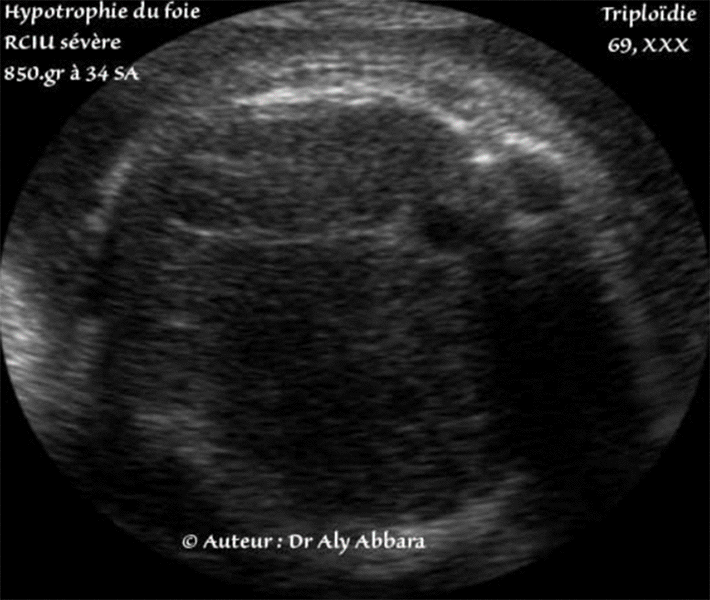

Hypotrophie du foie - Foetus ateint d'une triploïdie (69 chromosomes) - 34 SA

Hypotrophie hépatique chez un fœtus âgé de 34 SA, triploïde (69, xxx) et atteint

d'un retard de croissance intra-utérine sévère (poids estimé à 850 grammes).

• Coupe échographique abdominale transversale haute montrant le foie dans ses plus grandes dimensions, il s'agit d'un très petit foie par rapport à l'âge gestationnel de ce fœtus triploïde. L'hypotrophie hépatique est facilement décelable en comparant le périmètre du foie à celui de la vésicule biliaire, puis au périmètre abdominal.